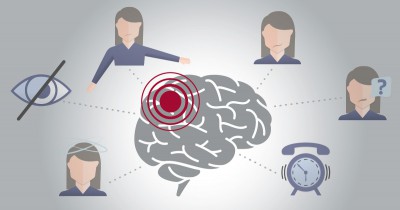

Đột quỵ ở người trẻ có dấu hiệu gia tăng

Đột quỵ ở người trẻ có dấu hiệu gia tăngTại Việt Nam, mỗi năm có khoảng 200.000 người bị đột quỵ. Trung bình cứ 6 người thì một người có nguy cơ đột quỵ. Bệnh này có thể xảy ra ở mọi lứa tuổi,...